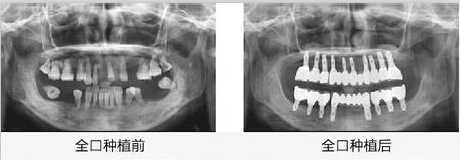

综合以上的优点,王老先生选择了种植牙手术进行了全口牙齿缺失的修复,经过修复后老先生吃饭也香了,牙龈上火的问题也解决了,整个人精气神都有了明显不同,为此家人们也非常开心。